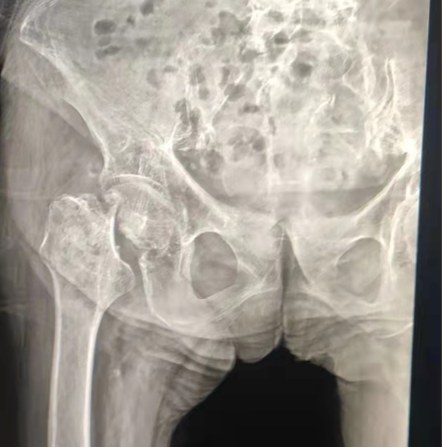

Case Sharing | Ein 70-jähriger Patient erhielt den gesamten Hüfte rsatz mit Lepu-Hüft system

Zementiertes Hüft system:

Co-Cr-Mo-Legierung materialien

Hohe Verschleiß festigkeit

Große mechanische Festigkeit

Schulter faden Design

Leicht installieren, halten und Winkel justieren

Polierte Oberflächen behandlung

Um ein aus gezeichnetes Knochen einwachsen zu erreichen Gewährleistung der Stabilität der frühen Fixierung

12/14 Standard-Verjüngung design

Proximal Mix Anatomy

Design-Kollektion Europa und USA Stem Features

Distal Beide Seiten Adge Cutting Behandlung

Reduzieren Sie den Druck in der Mark höhle